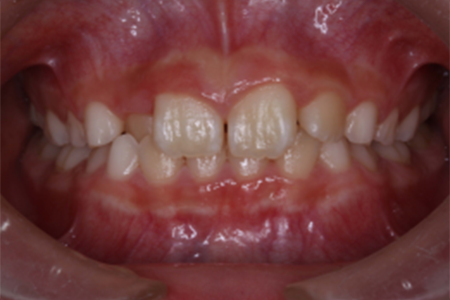

| 治療の経緯 | お母さまが子供の前歯の歯並びが気になるとのことで来院。 |

| 治療方法 | 右上2番が内側に入り込んでいる、部分的な反対咬合でしたので、 永久歯にだけ矯正装置をつけ、ワイヤーの力で、歯並びを改善しました。 |

| 治療期間 | 8ヵ月 |

|---|---|

| 費用 | インプラント 37万円×2本 骨造成 15万円 インプラント補綴 メタルボンド 15万円 |